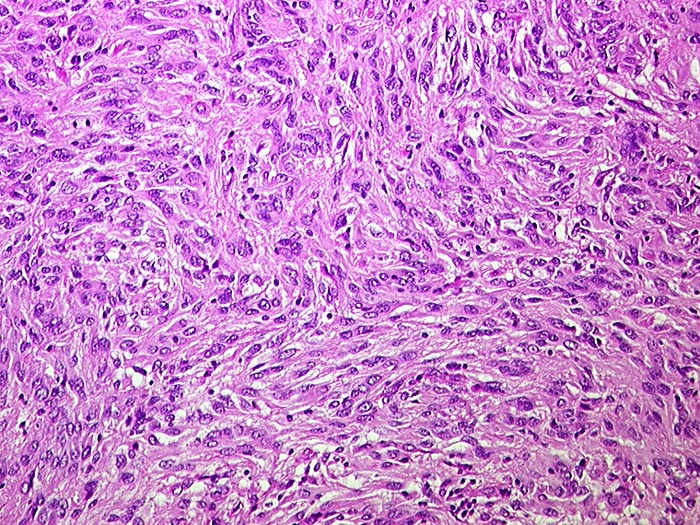

Morphologische Merkmale:

• Der Tumor besteht aus längs und quer getroffenen Faszikeln spindelförmiger Tumorzellen, welche an glatte Muskelzellen oder Schwannzellen erinnern.

• Herdförmig pseudozystische Auflockerung des Tumorgewebes.